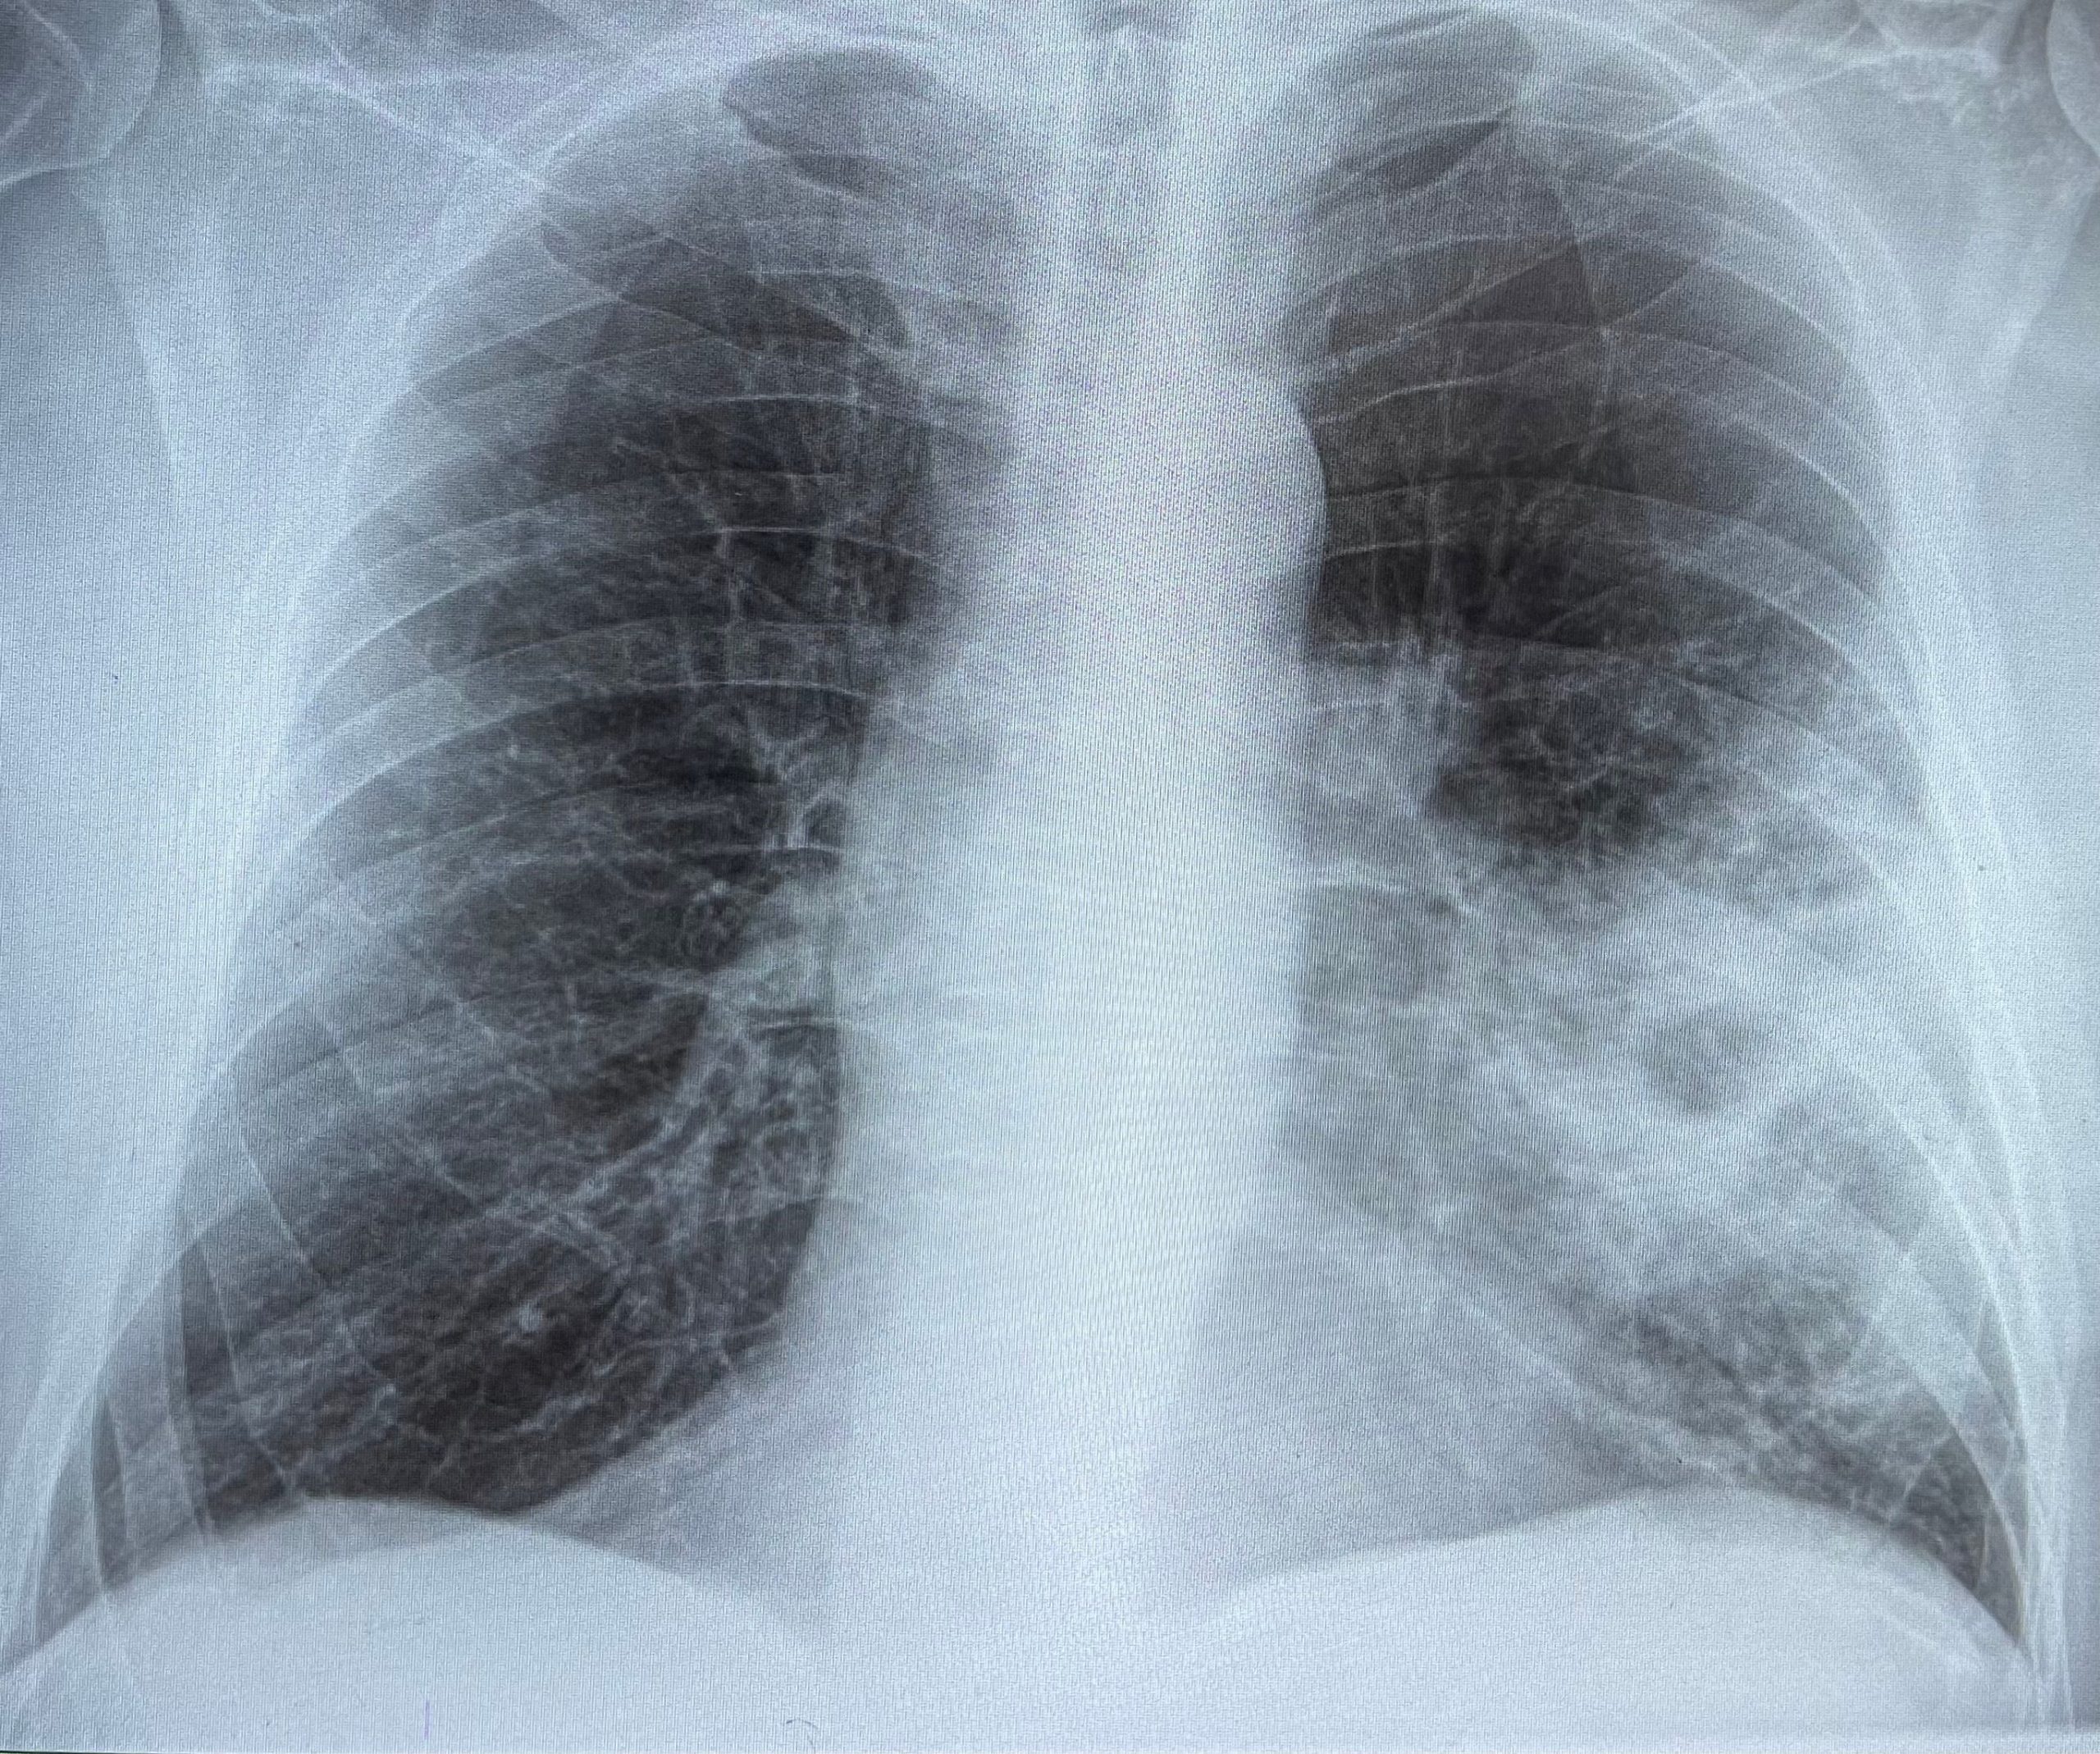

Zboli lahko vsak, najbolj ogroženi pa ravno kronični bolniki in starejši ljudje. Pri starejši populaciji okužba najpogosteje poteka v obliki pljučnice, lahko pa pride tudi do okužbe krvi in vnetja možganskih ovojnic oz. meningitisa. Nekatere hujše pnevmokokne okužbe se žal lahko končajo tudi s smrtjo.

Kot pravi prim. Katarina Osolnik, specialistka interne medicine in pnevmologije s Klinike Golnik, se največji delež pljučnic domačega okolja pozdravi na primarni ravni, medtem ko bolnišnice zdravijo najtežje primere. Na leto je v Sloveniji diagnosticiranih več kot 6000 bolnikov z diagnozo bolnišnične pljučnice.

Veliko ljudi ima pljučnico za nenevarno bolezen, ki jo pozdraviš z antibiotikom. Zlasti mlajši so presenečeni, kako težek je lahko potek. Zato je treba opozoriti, da je pljučnica resna bolezen. K sreči je smrtni izid redek, a se lahko zgodi – tudi pri mlajših.

Na Kliniki Golnik se vedno znova srečujejo z bolniki, ki jih zdravijo zaradi težje potekajoče pljučnice in so starejši od 65 let. Študije dokazujejo, da je prav populacija po 65. letu tudi zaradi različnih pridruženih bolezni toliko bolj ogrožena. Žal je verjetnost, da bo pri starostnikih prišlo do resnejših zapletov od trikrat do sedemkrat hitreje, če imajo starostniki pridružene bolezni, kot so sladkorna bolezen, srčno-žilne bolezni ali bolezni dihal.

V Sloveniji letno beležimo okoli 10.000 okužb, od tega petina bolnikov potrebuje bolnišnično oskrbo – približno 20-odstotkov od teh pa je premeščenih tudi na oddelke intenzivne nege. Prav pri slednjih je smrtnost še posebej visoka. Še znatno večja pa je umrljivost pri hospitaliziranih bolnikih s pljučnico, ki imajo pridružene kronične bolezni in pri tistih, ki potrebujejo obravnavo v enotah za intenzivno zdravljenje (20 do 50 %), kot je prebrati v zborniku Sekcije za protimikrobno zdravljenje pri SZD, Infektološki simpozij 2021.

Pri težje in najtežje potekajočih pljučnicah je lahko umrljivost tudi do 20 %. “Ni veliko diagnoz, ki bi imele tolikšno hospitalno umrljivost,” dodaja Osolnikova. Tudi zato se starejši pljučnice še vedno bojijo.

Pljučnica je še vedno pomemben vzrok smrti. Smrtnost v bolnišnici zdravljenih bolnikov s pljučnico je 10 % ali več, še znatno večja pa je pri hospitaliziranih bolnikih s pljučnico, ki imajo pridružene kronične bolezni in pri tistih, ki potrebujejo obravnavo v enotah za intenzivno zdravljenje (20 do 50 %), kot je prebrati v zborniku Sekcije za protimikrobno zdravljenje pri SZD, Infektološki simpozij 2021.